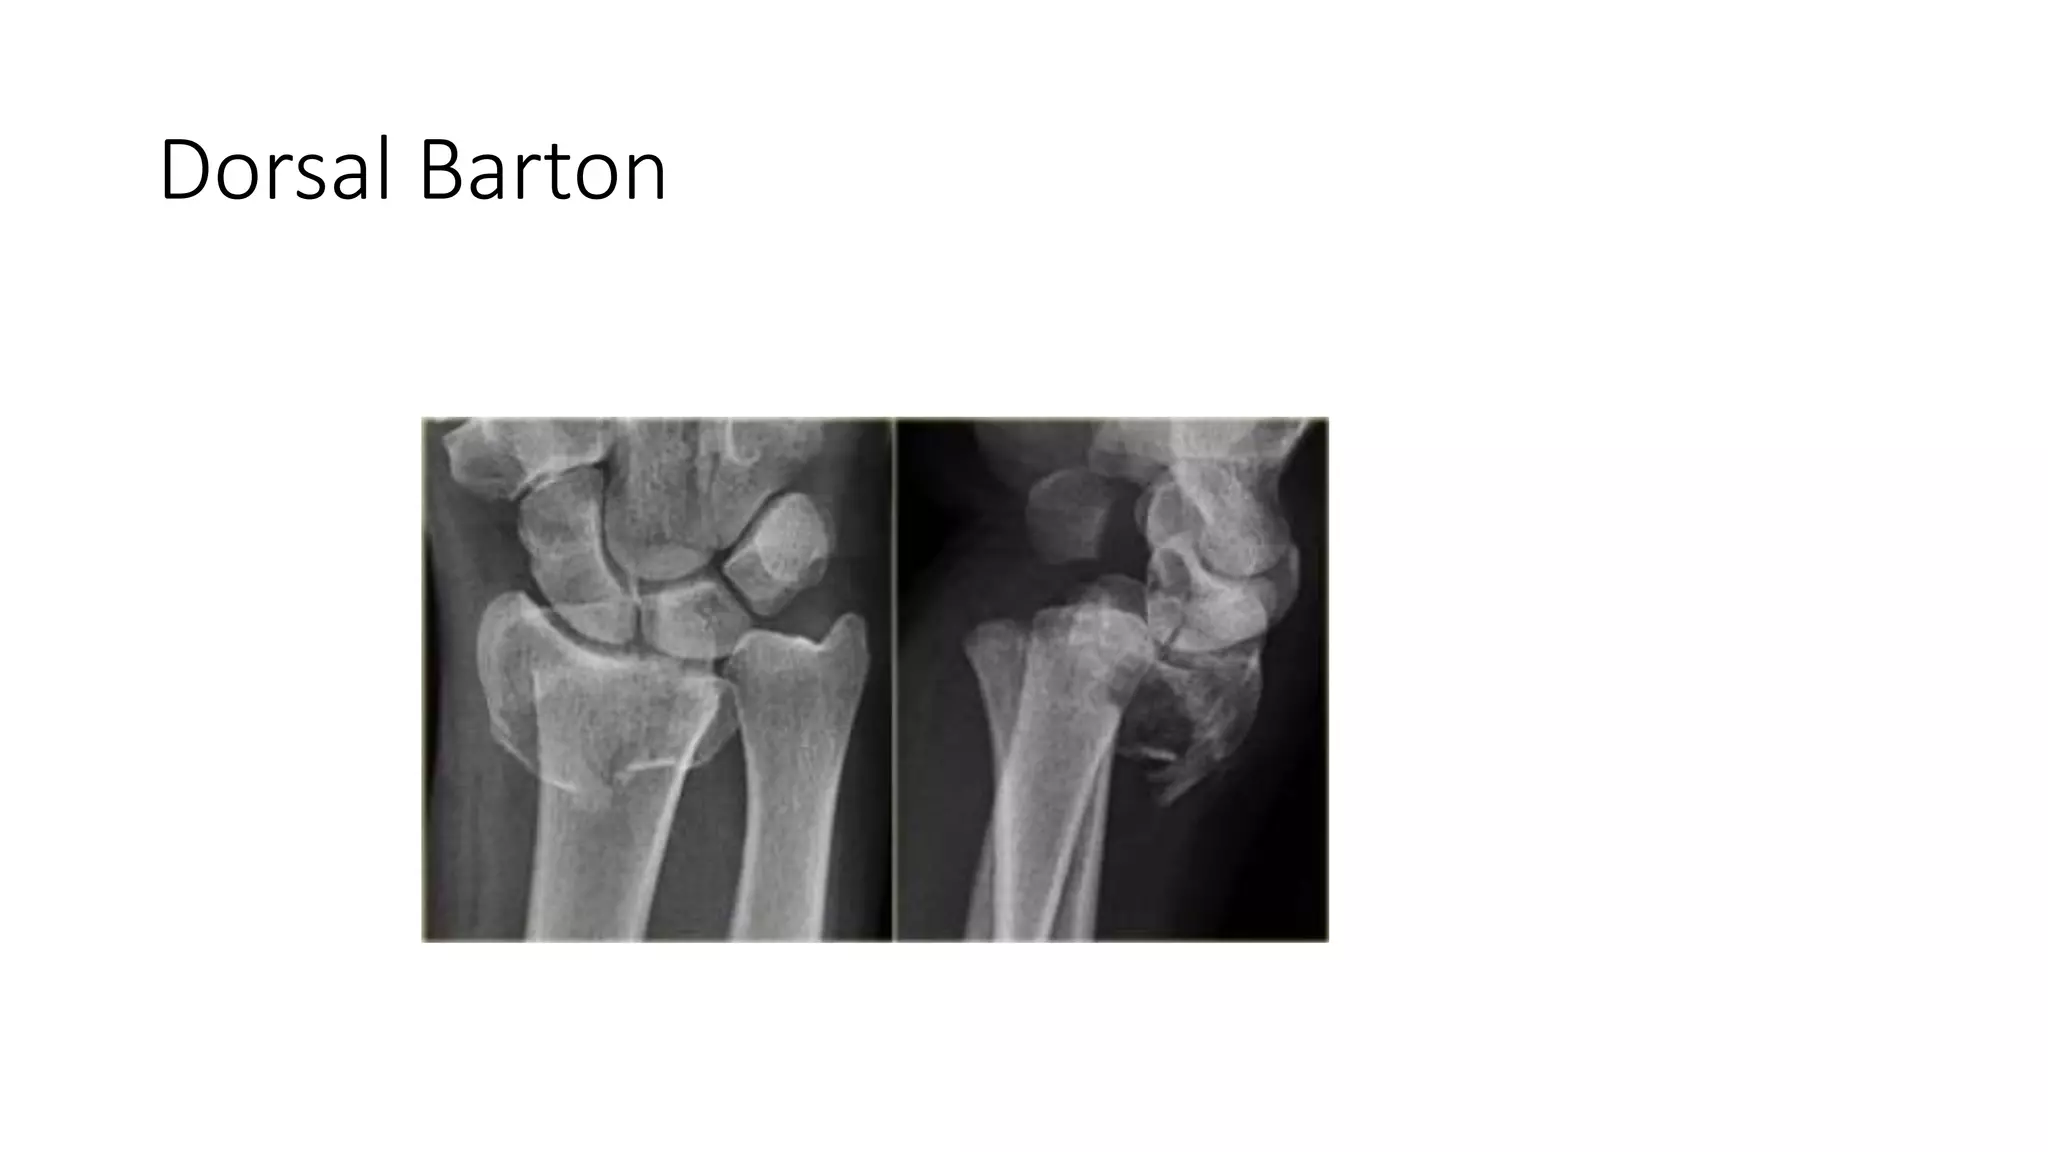

Volar and Dorsal Barton fractures — OrthopaedicPrinciples.com

Fractures of the distal radial physis and barton's fracture | PPTX

Fractures of the distal radial physis and barton's fracture | PPT